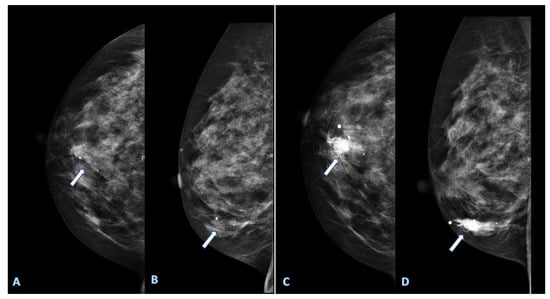

- Li, H.; Mendel, K.R.; Lan, L.; Sheth, D.; Giger, M.L. Digital Mammography in Breast Cancer: Additive Value of Radiomics of Breast Parenchyma. Radiology 2019, 291, 15–20. [Google Scholar] [CrossRef] [PubMed]

- Tagliafico, A.S.; Valdora, F.; Mariscotti, G.; Durando, M.; Nori, J.; La Forgia, D.; Rosenberg, I.; Caumo, F.; Gandolfo, N.; Houssami, N.; et al. An exploratory radiomics analysis on digital breast tomosynthesis in women with mammographically negative dense breasts. Breast 2018, 40, 92–96. [Google Scholar] [CrossRef]

- Tan, H.; Wu, Y.; Bao, F.; Zhou, J.; Wan, J.; Tian, J.; Lin, Y.; Wang, M. Mammography-based radiomics nomogram: A potential biomarker to predict axillary lymph node metastasis in breast cancer. Br. J. Radiol. 2020, 93, 20191019. [Google Scholar] [CrossRef]

- Yang, J.; Wang, T.; Yang, L.; Wang, Y.; Li, H.; Zhou, X.; Zhao, W.; Ren, J.; Li, X.; Tian, J.; et al. Preoperative Prediction of Axillary Lymph Node Metastasis in Breast Cancer Using Mammography-Based Radiomics Method. Sci. Rep. 2019, 9, 4429. [Google Scholar] [CrossRef]

- Mao, N.; Yin, P.; Zhang, H.; Zhang, K.; Song, X.; Xing, D.; Chu, T. Mammography-based radiomics for predicting the risk of breast cancer recurrence: A multicenter study. Br. J. Radiol. 2021, 94, 20210348. [Google Scholar] [CrossRef] [PubMed]